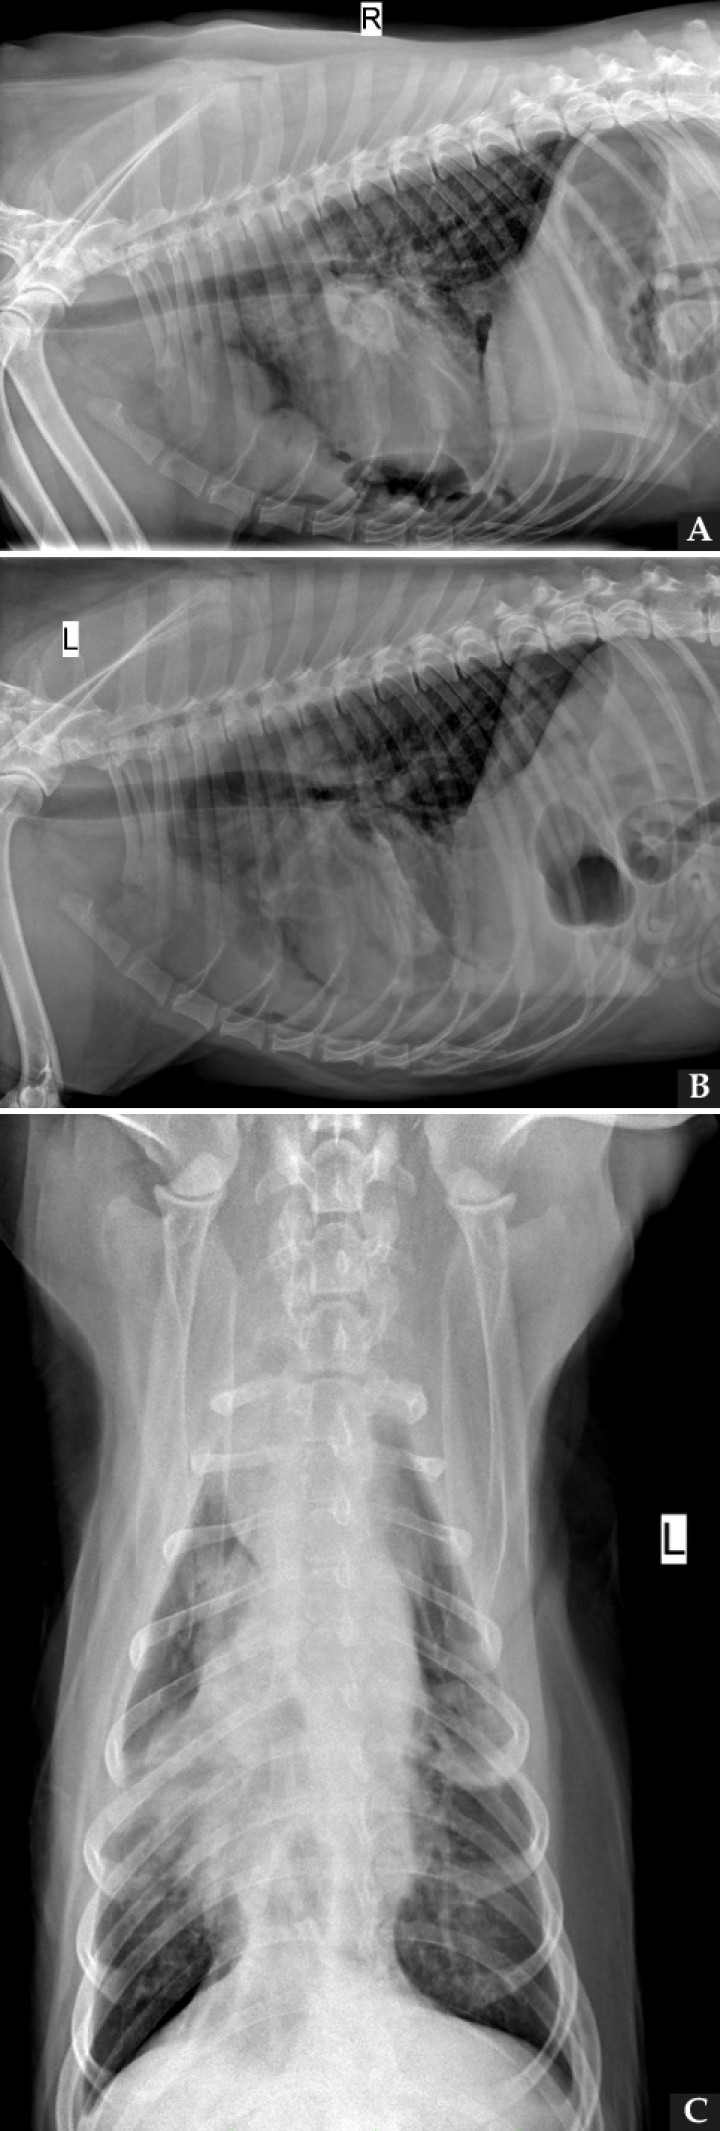

Tras la estabilización del paciente se realizaron tres proyecciones radiográficas del tórax (Fig. 1).

<p>Radiografías de la cavidad torácica de un perro mestizo de 9 años. (<strong>A</strong>) Proyección lateral derecha. (<strong>B</strong>) Proyección lateral izquierda. (<strong>C</strong>) Proyección ventrodorsal.</p>

Radiografías de la cavidad torácica de un perro mestizo de 9 años. (A) Proyección lateral derecha. (B) Proyección lateral izquierda. (C) Proyección ventrodorsal.

Se observa la presencia de una silueta de opacidad líquido/tejido blando, márgenes irregulares y poco definidos, que provoca un aumento marcado de la anchura del mediastino craneal (>2 veces el ancho de la columna vertebral) en la proyección ventrodorsal (VD), localizada en el aspecto ventral del mediastino craneal (Fig. 2). Dicha lesión produce un moderado efecto masa y desplaza la tráquea en sentido dorsal en las proyecciones laterales, así como la silueta cardiaca y los lóbulos pulmonares craneales en sentido caudodorsal compatible con una masa mediastínica.

<p>Mismas imágenes que en Figura 1. Se observa una silueta de opacidad líquido/tejido blando (asteriscos negros) en el mediastino craneoventral, produciendo elevación dorsal de la tráquea (flecha negra) y desplazamiento en sentido caudodorsal de la silueta cardiaca (flechas blancas) (<strong>A</strong> y <strong>B</strong>). Además, se aprecia atelectasia del lóbulo medio derecho (flechas amarillas) (<strong>C</strong>) y pequeñas estructuras de opacidad gas (asterisco blanco) (<strong>A</strong>).</p>

Mismas imágenes que en Figura 1. Se observa una silueta de opacidad líquido/tejido blando (asteriscos negros) en el mediastino craneoventral, produciendo elevación dorsal de la tráquea (flecha negra) y desplazamiento en sentido caudodorsal de la silueta cardiaca (flechas blancas) (A y B). Además, se aprecia atelectasia del lóbulo medio derecho (flechas amarillas) (C) y pequeñas estructuras de opacidad gas (asterisco blanco) (A).

Los lóbulos pulmonares caudales presentan los bordes redondeados debido al derrame pleural remanente tras el drenaje (Fig. 2). Además, se visualizan varias estructuras de densidad gas en el aspecto caudoventral del tórax, superpuesto parcialmente con la silueta cardiaca. Dicho gas puede ser de origen mediastínico o pleural, posiblemente yatrogénico. Se aprecia un moderado patrón bronco-intersticial generalizado con atelectasia del lóbulo medio derecho, sin evidencia de nódulos o masas pulmonares. La silueta cardiaca no presenta alteraciones reseñables (índice vertebral cardiaco: 10.2).

El resto de estructuras intra y extratorácicas visibles no muestran alteraciones evidentes.